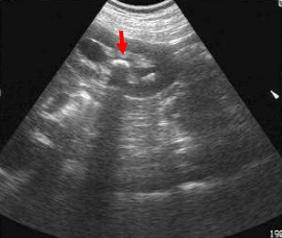

B超(筛查首选、廉价、无辐射);

B超是诊断尿路结石的首选检查,箭头所示为肾结石,强回声后伴声影